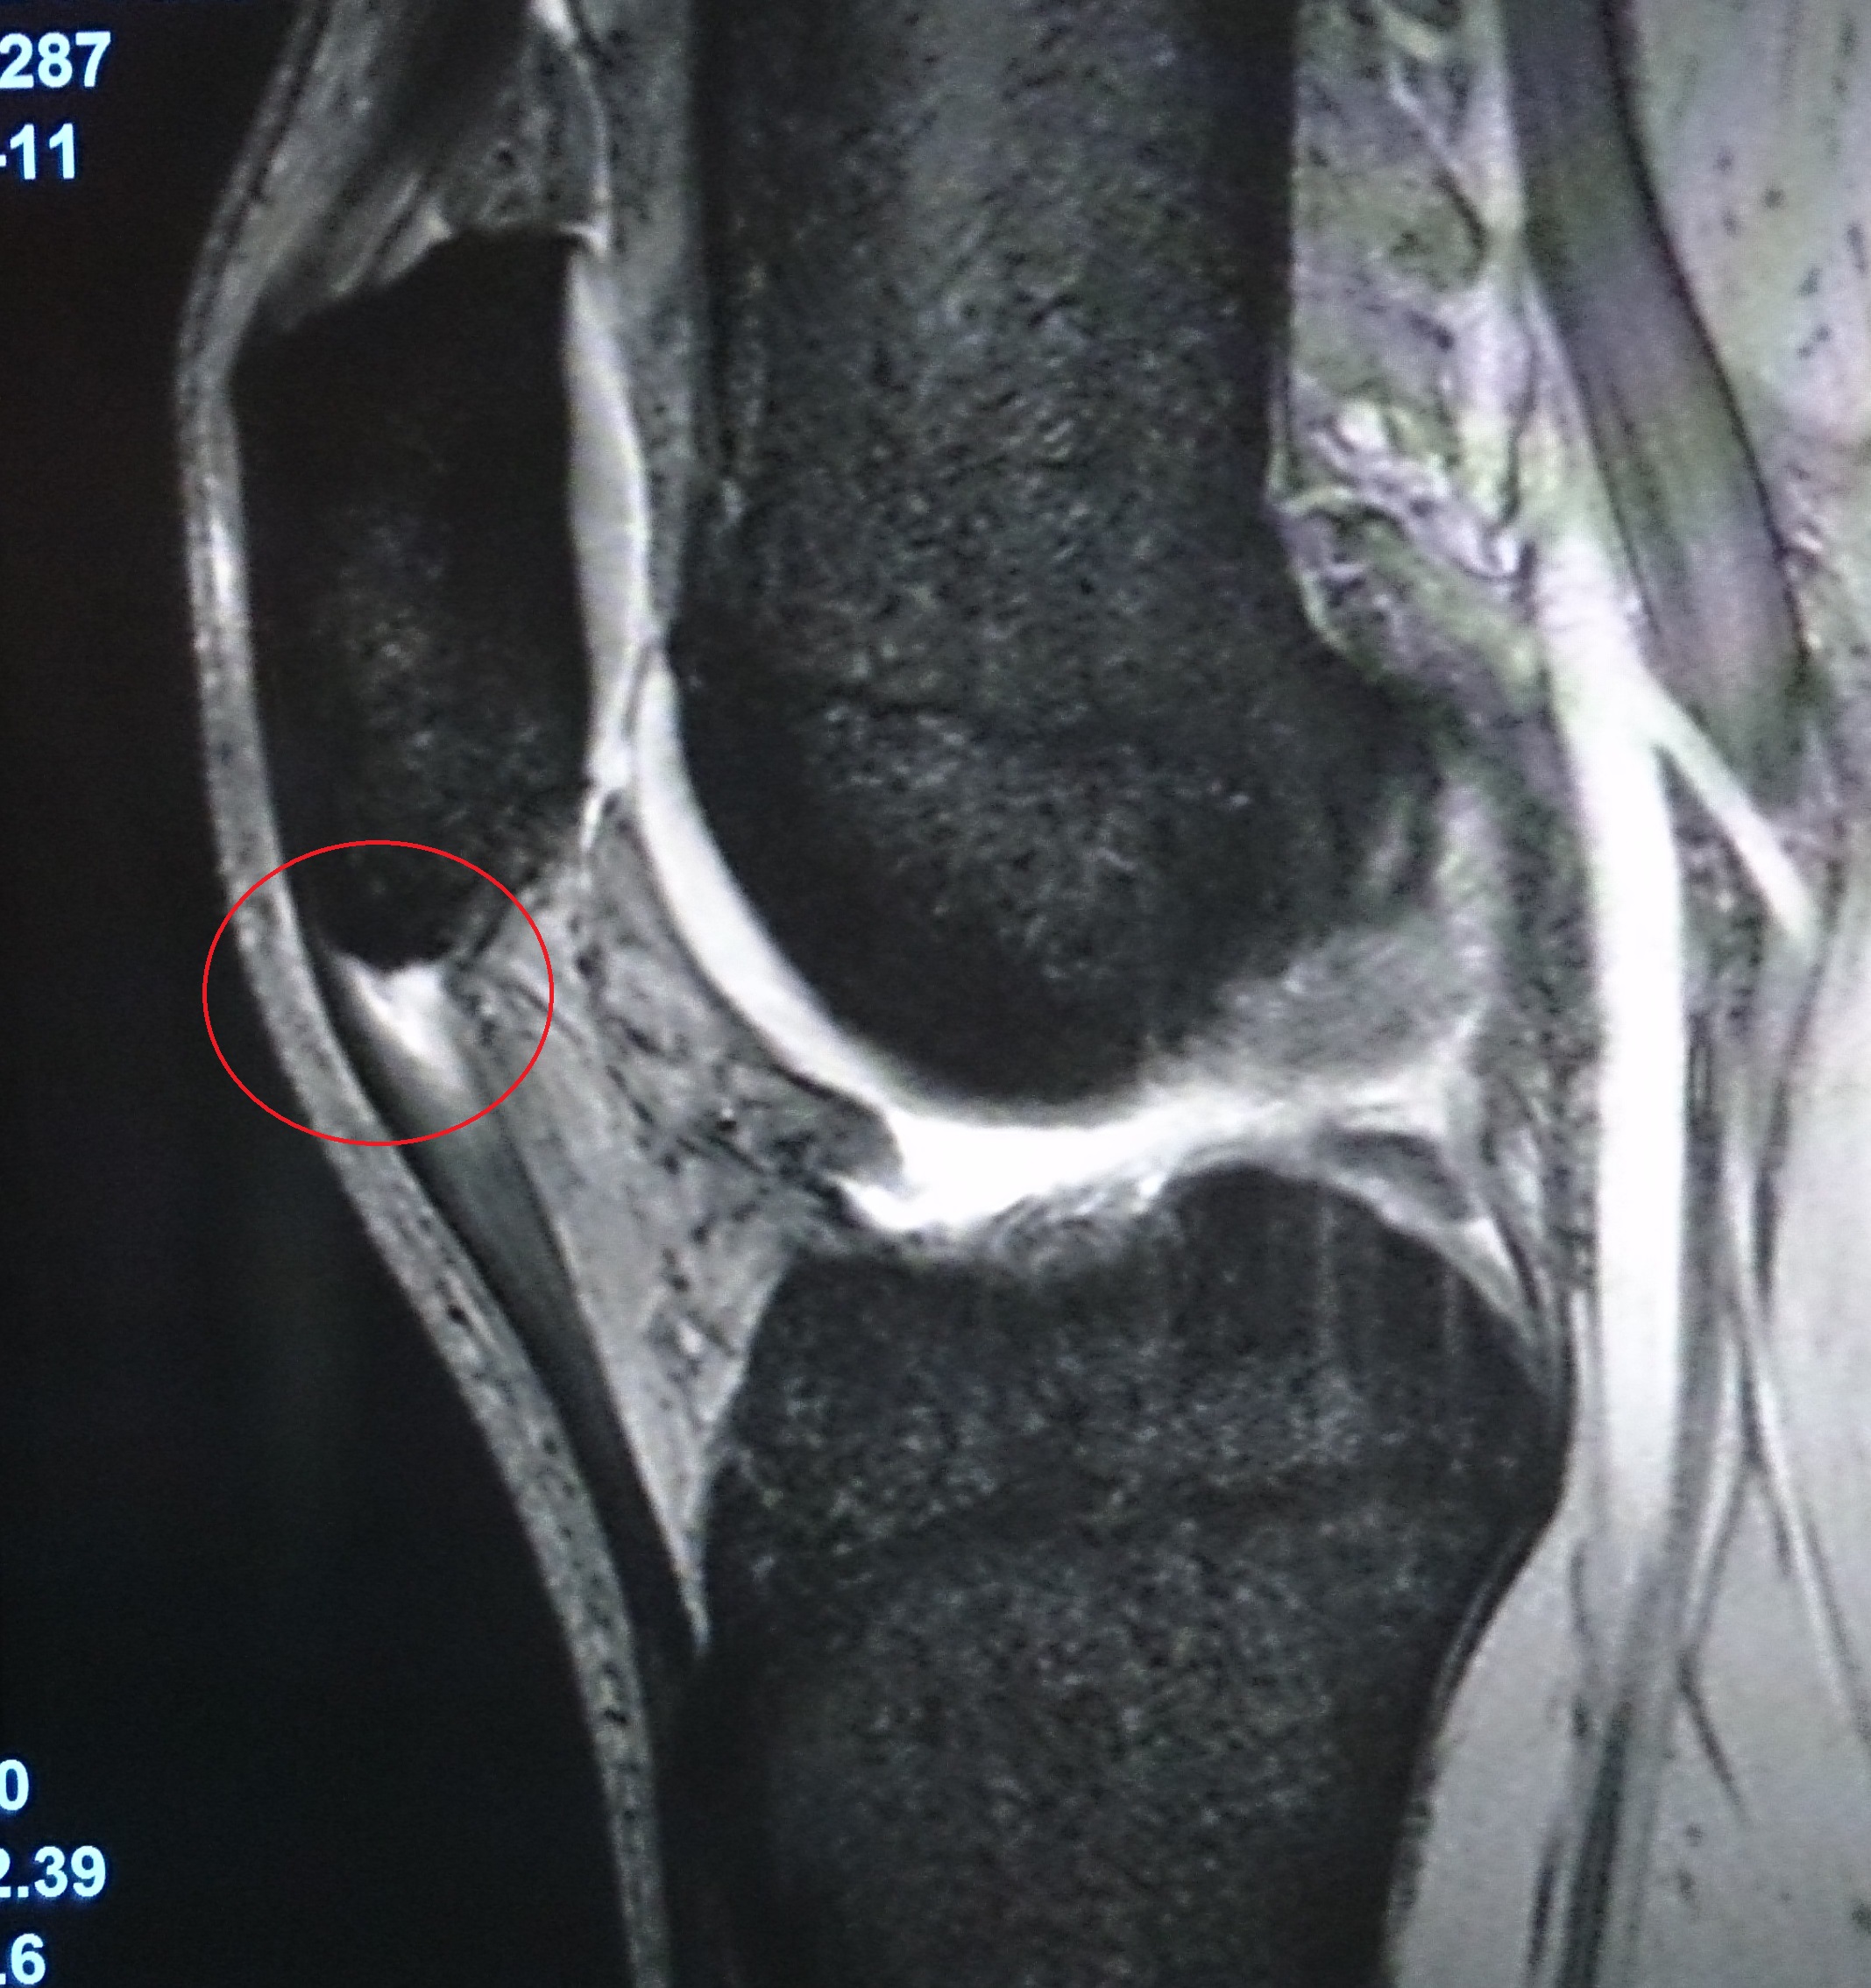

バレーボールチームのメディカルチェックを行った結果、腱の形態は、膝蓋骨下極を中心に全例肥厚像(健常例は3〜4mmの均一な帯状低信号)を呈しました。なかでも膝蓋骨下極で平均8.4mm(健常比227%)と最も太く、中間部で5.3(123%)、脛骨租面で4.9(113%)でした(写真3)。

写真3 女子バレーボール選手の膝のMRI(本文中「MRI所見」参照)